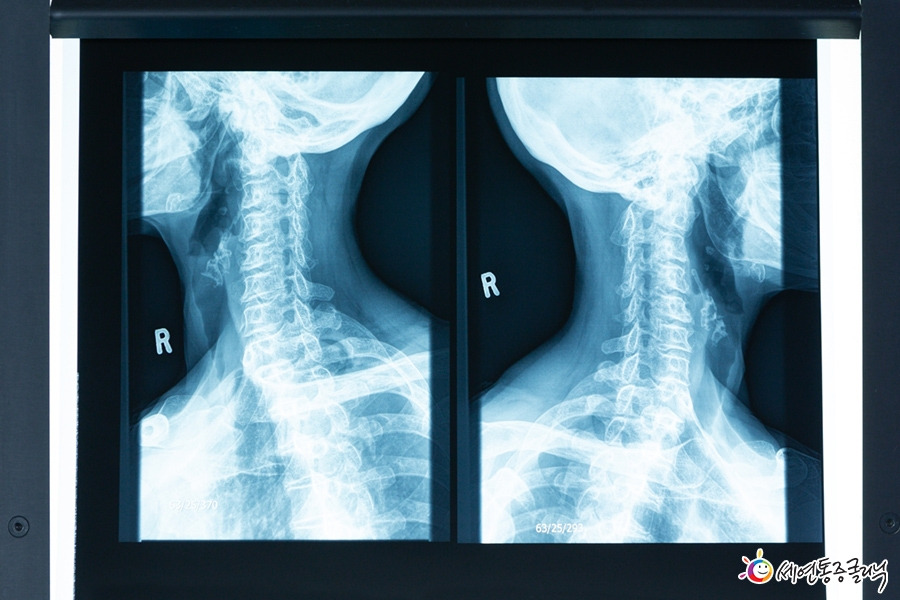

정상적인 목뼈는 C자형이지만, 이처럼 나쁜 자세를 장시간 유지하면 점점 일자목(일자형)이나 거북목(역 C자형)으로 목뼈 모양이 변형되어 뒷목과 어깨 근육까지 영향을 끼칩니다.

정상적인 C자형 목뼈는 머리의 하중을 자연스럽게 분산시켜주고 충격을 완화해주지만, 일자목이나 거북목증후군 환자의 목뼈는, 정상적인 C자형 목뼈보다 충격을 완화하는 능력이 현저히 떨어집니다.

게다가 머리의 무게가 분산되지 않은 채 그대로 목-어깨-허리까지 직접적으로 전달되어, 경추 추간판(디스크)이 압력을 받아 결국 목디스크를 유발하는 원인이 되는 것입니다.